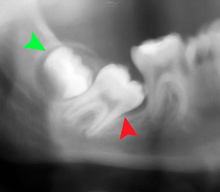

If the tooth cannot be assessed with clinical exam alone, the diagnosis is made using either a panoramic radiograph or cone-beam CT. Where unerupted wisdom teeth still have eruption potential several predictors are used to determine the chance of the teeth becoming impacted. The ratio of space between the tooth crown length and the amount of space available, the angle of the teeth compared to the other teeth are the two most commonly used predictors, with the space ratio being the most accurate. Despite the capacity for movement into early adulthood, the likelihood that the tooth will become impacted can be predicted when the ratio of space available to the length of the crown of the tooth is under 1.[3]:141